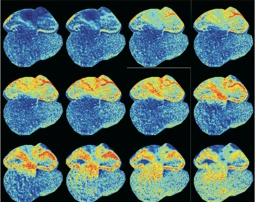

Marrying optics and genetics, optogenetics enables scientists to use light to trigger and monitor the behavior of cells engineered to contain one or both of two types of designer proteins: effectors, which respond to light by activating the cell they are on, or sensors, which fluoresce when a cell has been activated.

Effectors and sensors can be engineered into specific kinds of cells and color-coded, letting scientists noninvasively trigger one type to see how another type responds. One can see different cell types light up in living animals, giving direct insight into specific cells’ roles in complex biological systems.

“For example, our lab is particularly interested in using these tools to study the control of blood flow to tissues – what happens before, during and after major events like stroke and cardiac infarction, and how abnormal rhythms develop after heart injury,” said Kotlikoff. “Arrhythmias following a heart attack are the single most common cause of acute death in the western world, and how they can be prevented requires a better understanding of how, why and where they arise. Optogenetic tools let us look directly at relevant cells throughout the heart to determine their role in these dangerous and often fatal events.”